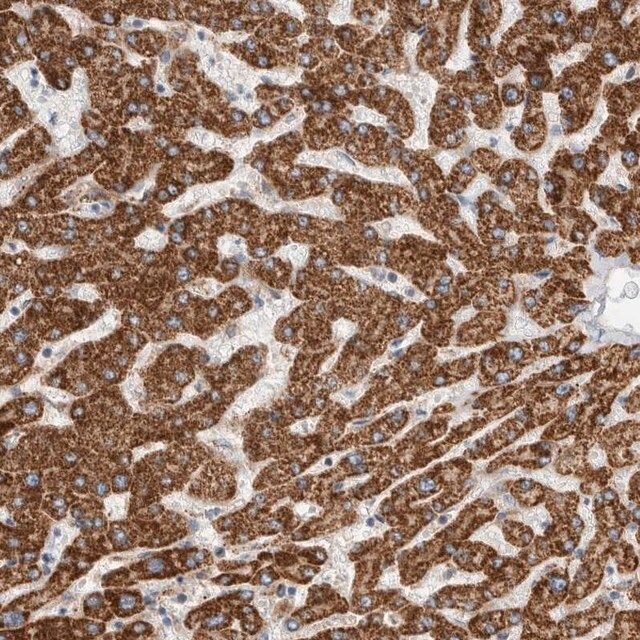

The Human Protein Atlas project can be subdivided into three efforts: Human Tissue Atlas, Cancer Atlas, and Human Cell Atlas. The antibodies that have been generated in support of the Tissue and Cancer Atlas projects have been tested by immunohistochemistry against hundreds of normal and disease tissues and through the recent efforts of the Human Cell Atlas project, many have been characterized by immunofluorescence to map the human proteome not only at the tissue level but now at the subcellular level. These images and the collection of this vast data set can be viewed on the Human Protein Atlas (HPA) site by clicking on the Image Gallery link. To view these protocols and other useful information about Prestige Antibodies and the HPA, visit sigma.com/prestige.

- IHC tissue array of 44 normal human tissues and 20 of the most common cancer type tissues.